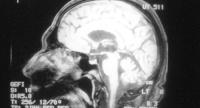

رجل يصاب بجلطة في المخ عقب50 ساعة داخل مقهى إنترنت